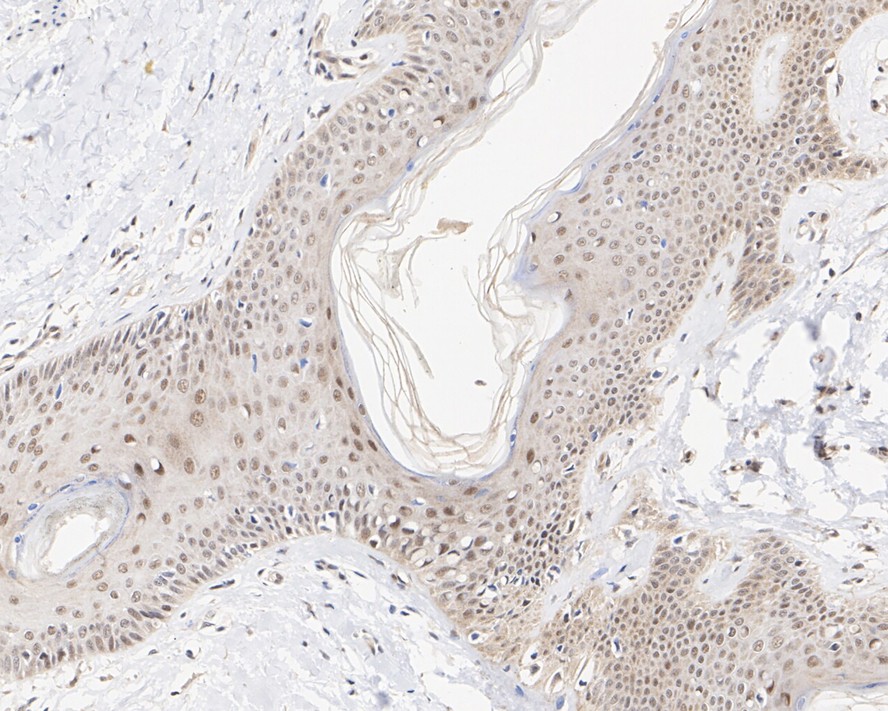

Immunohistochemical analysis of paraffin-embedded human skin tissue with Mouse anti-BRCA1 antibody (HA610177) at 1/1,000 dilution.

The section was pre-treated using heat mediated antigen retrieval with sodium citrate buffer (pH 6.0) (high pressure) for 2 minutes. The tissues were blocked in 1% BSA for 20 minutes at room temperature, washed with ddH2O and PBS, and then probed with the primary antibody (HA610177) at 1/1,000 dilution for 1 hour at room temperature. The detection was performed using an HRP conjugated compact polymer system. DAB was used as the chromogen. Tissues were counterstained with hematoxylin and mounted with DPX.